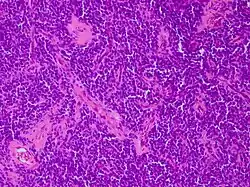

Los tumores vaginales son neoplasias que se encuentran en la vagina. Pueden ser benignos o malignos.[1] Una neoplasia es un crecimiento anormal de tejido que generalmente forma una masa de tejido.[2][3][4] Las neoplasias vaginales pueden ser sólidas, quísticas o de tipo mixto.[5]

Tumor vaginal Benigno Referencias Tumor Yolk sac no [16][17][18][19][20][21][22] Tumor neuroectodérmico primitivo Periferal no [16][17][18][23] Melanoma vaginal no [16][17][18][24][25] Blue nevus sí[26] [16][17][18][25] Carcinosarcoma no [18] Sarcoma botryoides no [9][16][17][18][22][27][28] Leimiosarcoma no [18][29] Sarcoma Endometrioide estromal no [18][30] Sarcoma vaginal no diferenciado [18] Leiomioma sí [6][13][16][17][18] Genital rhabdomyoma [16][17][18][31][32][33] Deep angiomyoxoma [16][17][18] Spindle cell nodule [9][16][17][18][34] Carcinoma no diferenciado [16][17][18] Carcinoma de células pequeñas no [16][17][18] Carcinoide no [18] Carcinoma Adenoide basal [18] Carcinoma Adenosquamous no [18] Adenoma sí [35] Adenocarcinoma mucinoso [18] Papilloma Squamous sí [16][17][18] Adenocarcinoma de endometrio no [18] Clear cell adenocarcinoma no [16][17][18] Pólipo fibroepiteleal sí [16][17][18] Squamous intraepithelial neoplasia [16][17][18] Verruga genital sí [6][16][17][18] Carcinoma espinocelular no [16][17][18] Mesenchymal tumors [18] Alveolar soft part sarcoma [18] Mixed epithelial and mesenchymal Tumors [18] Malignant mixed Tumors resembling synovial sarcoma [18] Tumores mezclados benignos [18] Adenomatoides sí [18] Linfoma maligno no [18] Sarcoma granulocítico [18] Fibroepithelial polyp sí [6][17] Verrucous carcinoma no [9] Squamotransitional cell carcinoma [9]